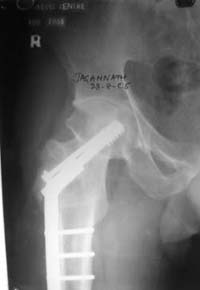

Dynamic hip screw with abduction osteotomy with an additional cancellous screw